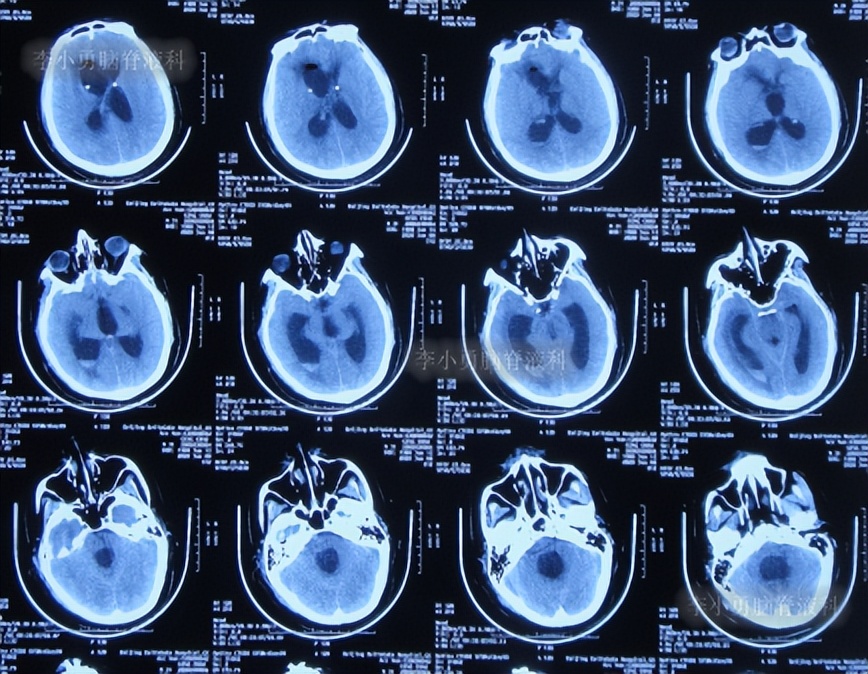

于2019年12月30日(鞍上池脑囊虫切除术+三脑室造瘘术后近2年,第3次出院后74天即脑室腹腔分流术后1年零9个月;又即脑室分流管探查调整术近3个月),第4次就诊于给予手术的医院,考虑脑积水加重。

入院次日2019年12月31日,进行了第2次的左侧脑室腹腔分流术(图-6)。

图-6:2019年12月31日头颅CT

术后患者症状慢慢缓解,但腰椎穿刺检查示脑脊液蛋白非常高,患者虽神志清楚,可是下颌不自主震颤,伴有复视。

第2次的左侧脑室腹腔分流术后10天即2020年1月10日,查头颅CT示脑室仍有扩张(图-7)。

图-7:2020年1月10日头颅CT

第2次的左侧脑室腹腔分流术后18天即2020年1月18日,查头颅CT示脑室有缩小(图-8)。

图-8:2020年1月18日头颅CT